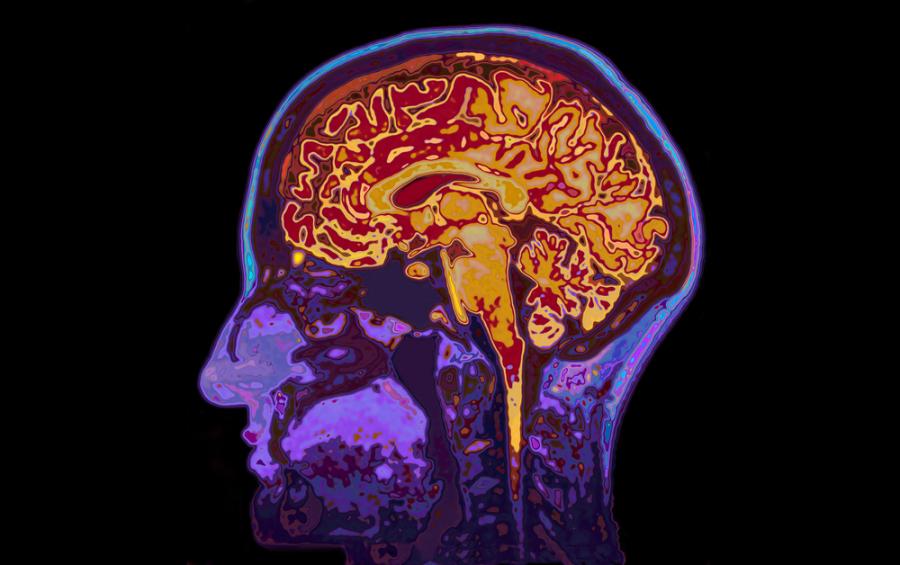

Нова терапия срещу изключително агресивен вид мозъчен тумор дава обещаващи резултати на ранен етап

Нова терапия за борба с изключително агресивен вид мозъчен тумор дава обещаващи резултати при няколко експеримента с малък брой пациенти, предаде Асошиейтед прес.